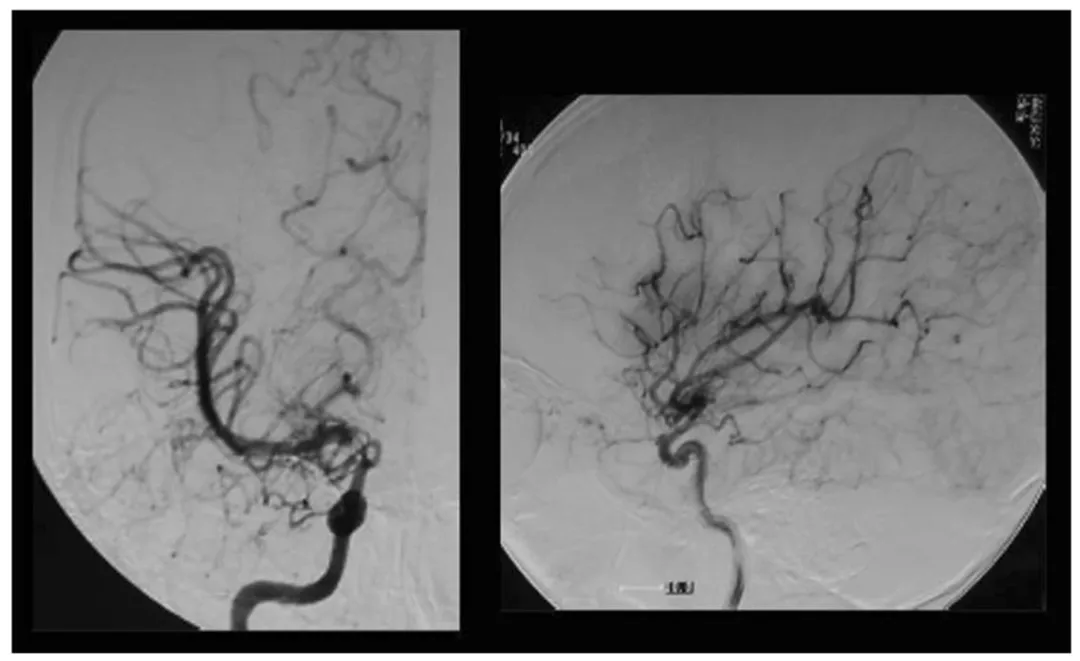

图1,术前右颈动脉血管造影显示IC末端顶部烟雾血管发育,左:前后视图,右:侧视图

血管造影检查显示,小优右侧颈内动脉末端已出现狭窄,颅内长出了细小的“烟雾状血管”,病情处于铃木分期II期(早期),且即将过渡到III期;左侧血管暂时无异常。